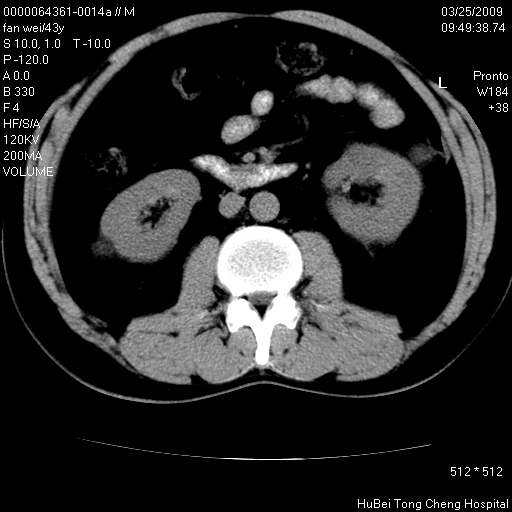

患者 男,43岁。左侧腰部不适两天。平素健康。无家族遗传病史。

腹部彩超提示:1)轻度脂肪肝。2)左肾多发囊性占位性病变;建议行进一步检查。

临床诊断:左肾多发囊性占位性病变,性质待定(多发肾囊肿?)。

双肾ct轴位平扫+增强扫描(层厚10mm,螺距1.0,重建间隔10mm),图像如下: